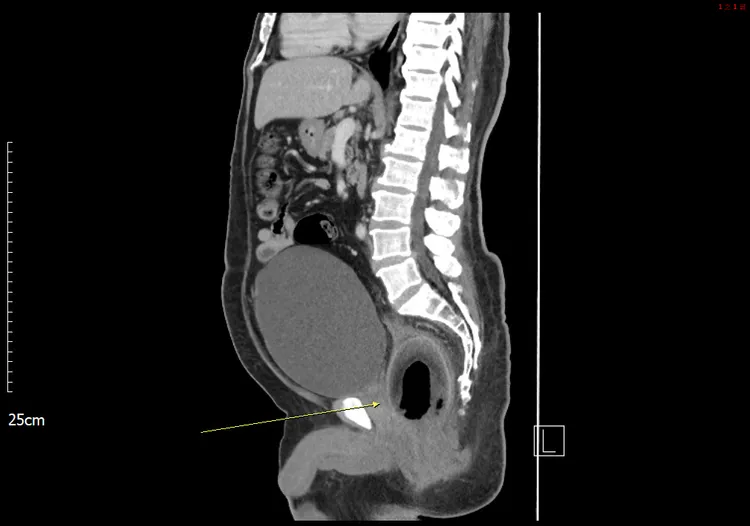

義大醫院表示,這名 56 歲男性患者,主訴腹痛 2 天,伴有無尿和嚴重便秘,但無其他症狀,如發燒、噁心或嘔吐。

院方體格檢查患者生命體徵穩定。腹部檢查發現,腹部膨脹、壓痛,有反彈痛。影像學檢查腹部電腦斷層掃描 (CT) 顯示,直腸內有一個巨大的異物,壓迫前列腺尿道,導致尿滯留。治療患者接受了探查性剖腹手術,從直腸中取出一個「椰子」,實際大小為7.5X5.7X5.5 公分。大腸直腸外科主治醫師陳致一寫成報告,向國際醫學期刊投稿,2023年1月刊登在英國外科雜誌 110 卷第一期,頁碼 123。